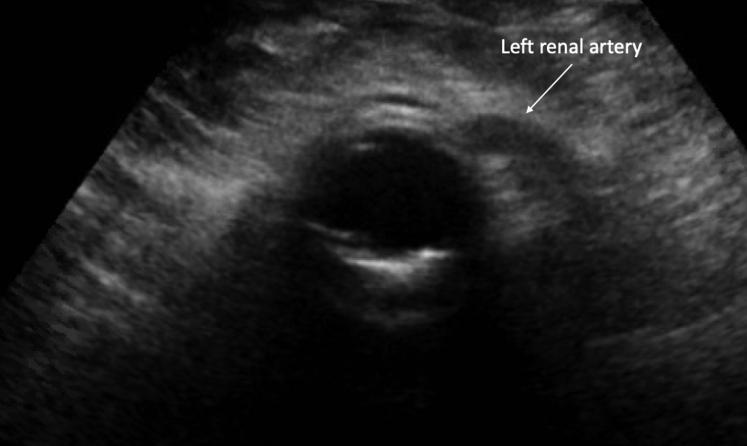

Secondary aortoenteric fistula is a potentially lethal complication after aortic surgery. Traditional treatment consists of open graft excision with extra-anatomic bypass or in situ reconstruction. Patients who present in extremis, however, are generally poor candidates for re-do open aortic surgery. Endovascular repair has emerged as an alternative treatment modality for patients who would otherwise be unable to tolerate an extended operation. We report here a case of urgent endovascular repair of a juxtarenal secondary aortoenteric fistula via endovascular aneurysm repair with a renal artery chimney in a patient with a solitary kidney who presented in hemorrhagic and septic shock.

Emergent percutaneous chimney endovascular aortic repair of a secondary aortoenteric fistula in the setting of a solitary kidney.